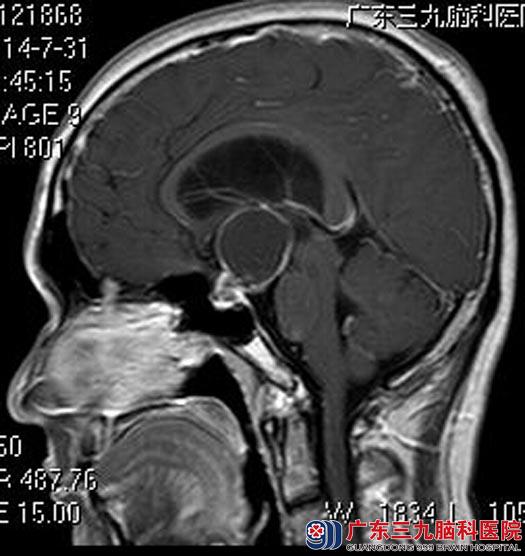

陈先生,间歇性头晕2个多月,偶尔会伴有头痛,当地医院检查提示鞍区占位。我院进一步头颅MRI检查发现:鞍区示一囊实性占位性病变,范围约3.23cm×3.02cm×4.01cm,视交叉及三脑室底部受压。

手术前